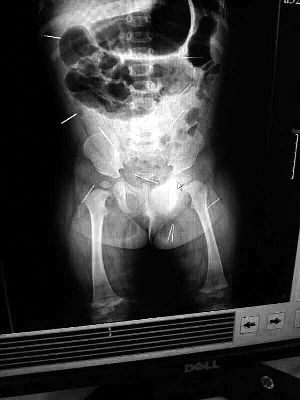

山東聊城11個(gè)月女?huà)胼孑妫ɑ┮伤票蝗艘?2根鋼針插滿臀部、腹腔等部位,昨天在兒童醫(yī)院會(huì)診后,醫(yī)生稱(chēng)3根針靠近胸腔最危險(xiǎn),首批先行取出,預(yù)計(jì)將在下周二手術(shù)。孩子父母稱(chēng)孩子一直由家人照顧,自家與他人并無(wú)冤怨。山東警方表示正在偵破中,不便透露案情。

“要不是當(dāng)初那幾個(gè)紅點(diǎn),可能到現(xiàn)在我們還不知道孩子身體里有鋼針!”昨天,在兒童醫(yī)院住院處,萱萱爸爸范先生稱(chēng),日前原本很愛(ài)笑的萱萱突然變得有些焦躁,一抱起來(lái)就哭,孩子母親偶然間在萱萱屁股上發(fā)現(xiàn)了幾個(gè)小紅點(diǎn)兒,原以為是蚊蟲(chóng)叮咬,就醫(yī)結(jié)果卻讓人不寒而栗?!搬t(yī)院拍出的片子上,萱萱的體內(nèi)有12根鋼針,插滿臀部、腹腔、骨盆等各個(gè)部位?!狈断壬榻B,因?yàn)殇撫樢焉钊塍w內(nèi),要是孩子不哭鬧,他們很難發(fā)現(xiàn)。

北京晨報(bào)記者了解到,目前體內(nèi)的12根鋼針多分布在孩子的臀部,一根在腹部,其余3根在胸腔附近,其中一根很接近心臟?!耙?yàn)楹⒆犹?,醫(yī)生們害怕取針的時(shí)候?qū)λ斐蓚?,在胸腔附近?針可能會(huì)威脅她的生命”。